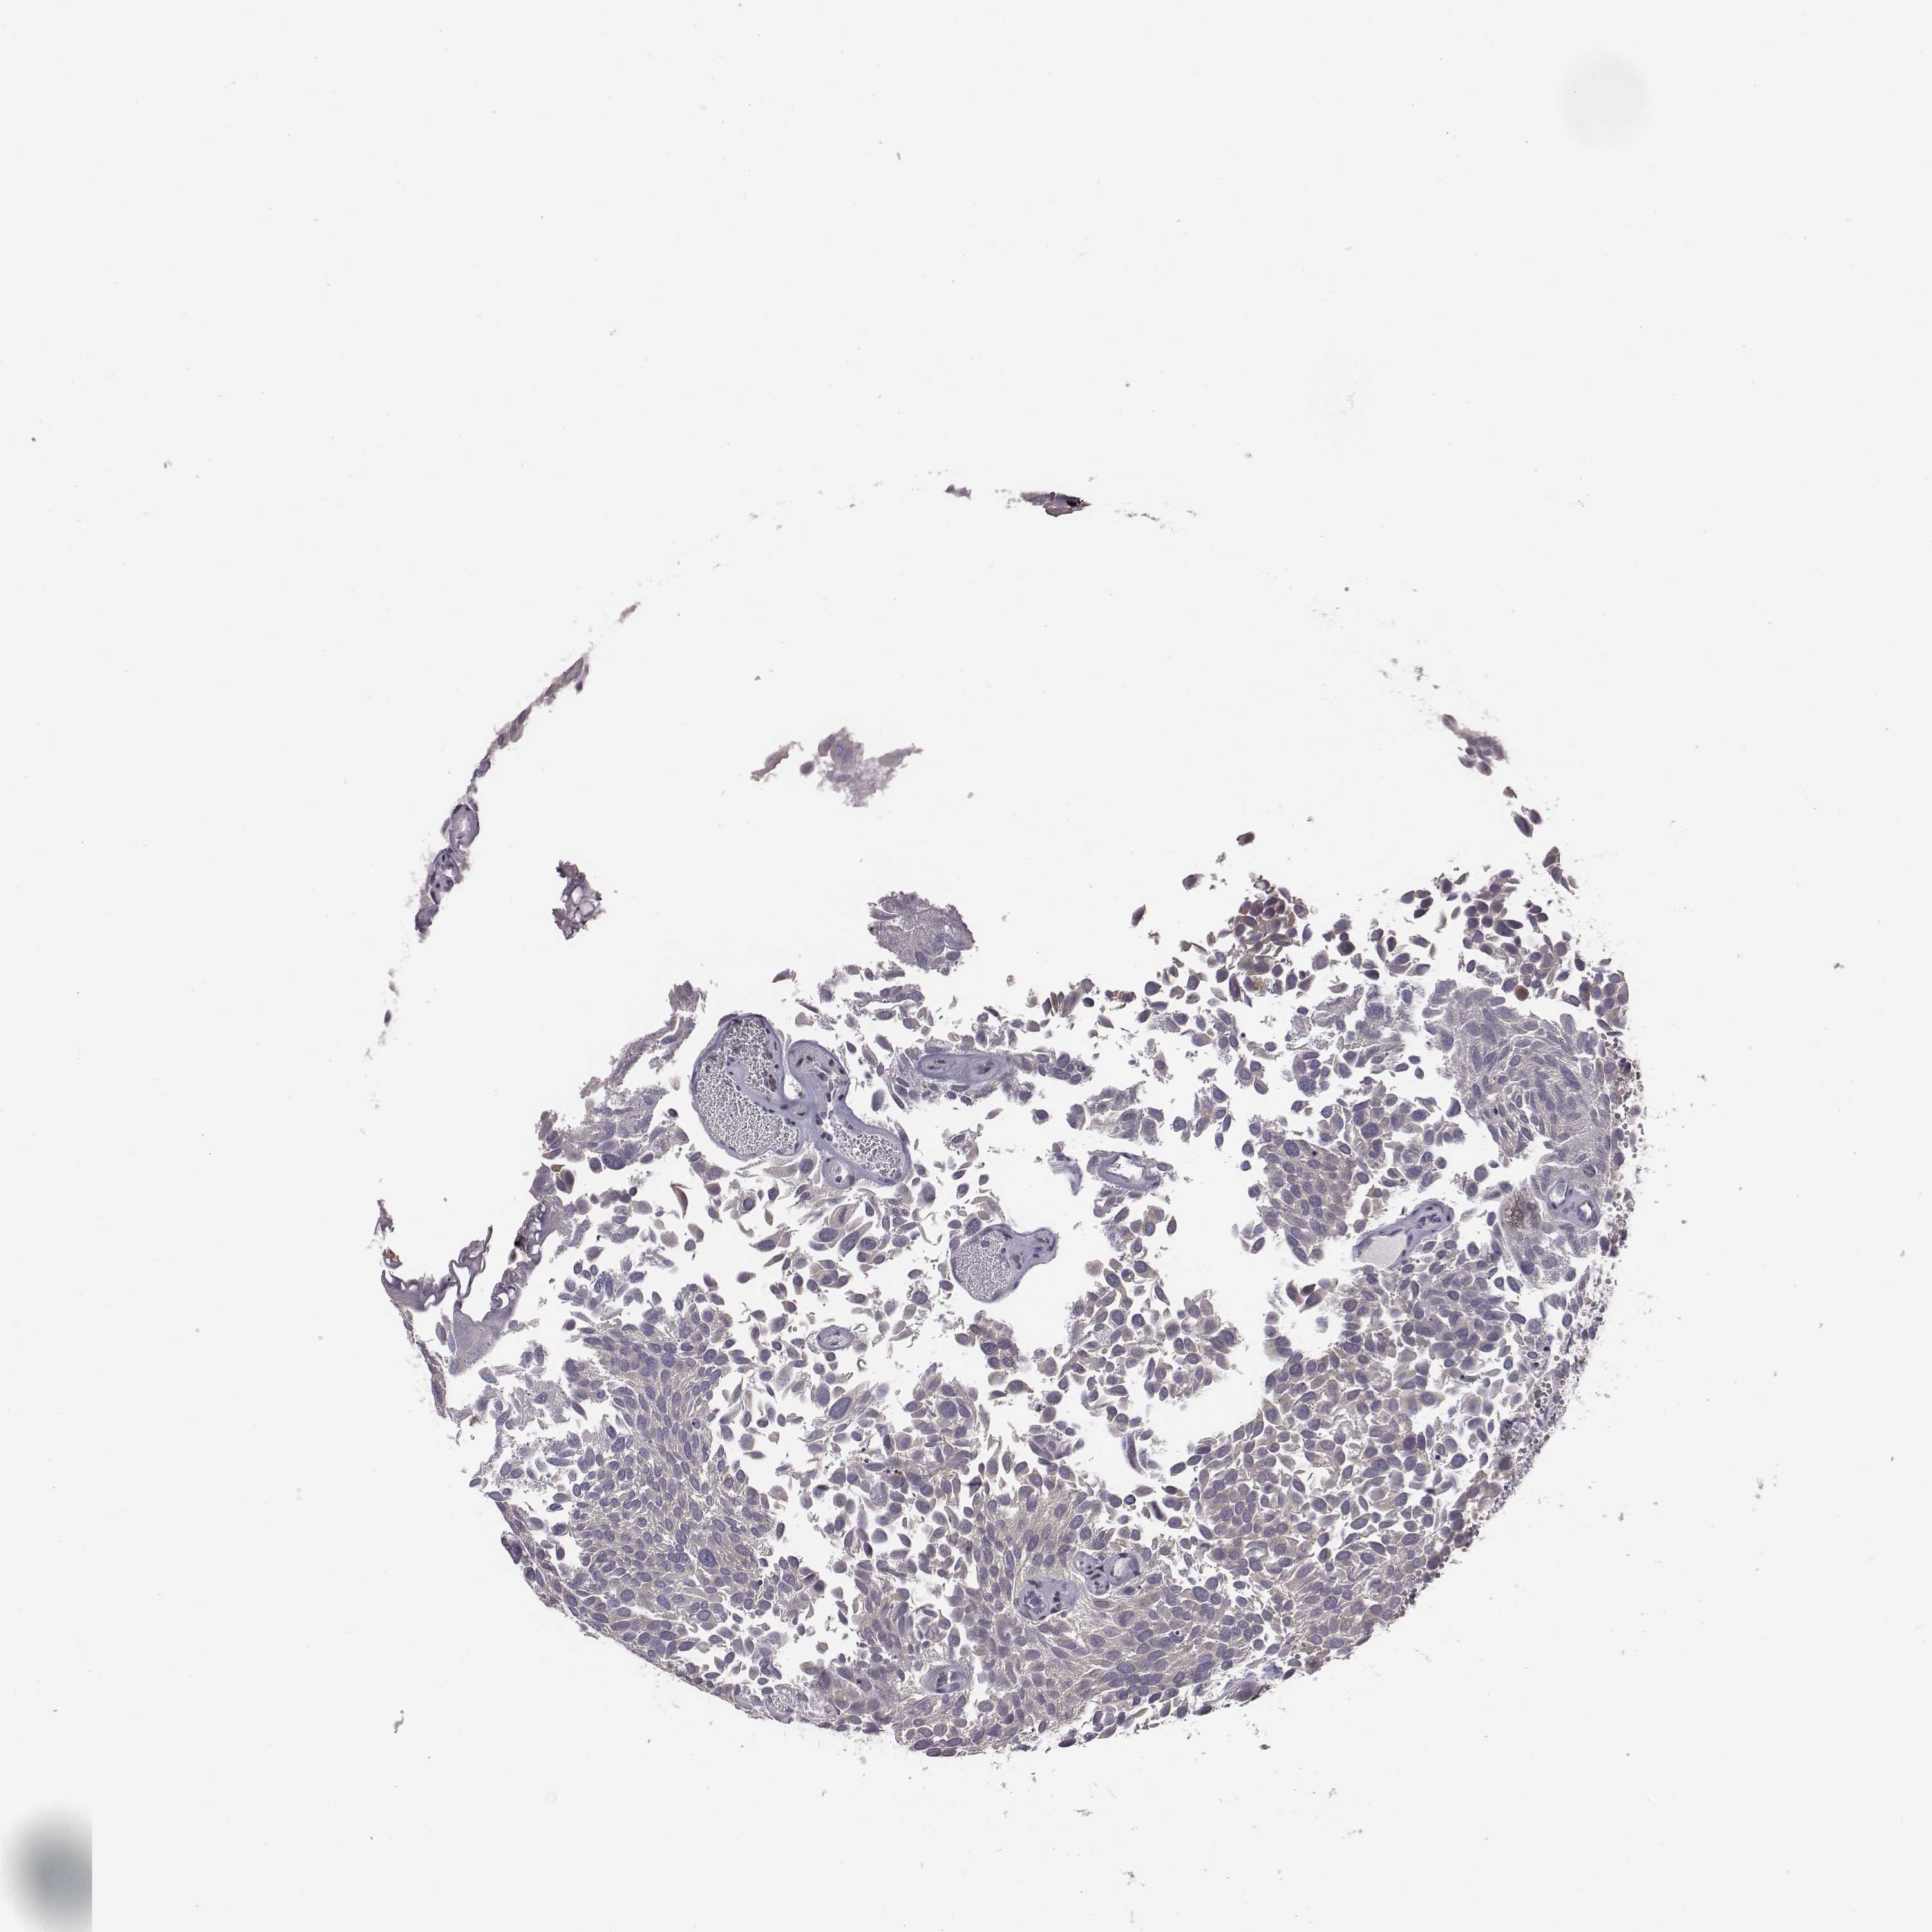

UROTHELIAL CANCER - Protein expressioni

A mouse-over function shows sample information and annotation data. Click on an image to view it in a full screen mode. Samples can be filtered based on level of antibody staining by selecting one or several of the following categories: high, medium, low and not detected. The assay and annotation is described here.

Note that samples used for immunohistochemistry by the Human Protein Atlas do not correspond to samples in the TCGA dataset.

Antibody stainingi

Antibody staining in the annotated cell types in the current human tissue is reported as not detected, low, medium, or high, based on conventional immunohistochemistry profiling in selected tissues. This score is based on the combination of the staining intensity and fraction of stained cells.

Each image is clickable and will lead to virtual microscopy that enables deeper exploration of all samples and also displays staining intensity scores, fraction scores and subcellular localization as well as patient and tissue information for each sample.

Antibody HPA071508

Staining

High

Medium

Low

Not detected

Intensity

Strong

Moderate

Weak

Negative

Quantity

>75%

75%-25%

<25%

None

Location

Nuclear

Cytoplasmic/membranous

Cytoplasmic/membranous,nuclear

Urothelial carcinoma, High grade

Urothelial carcinoma, NOS

Urothelial carcinoma, Low grade